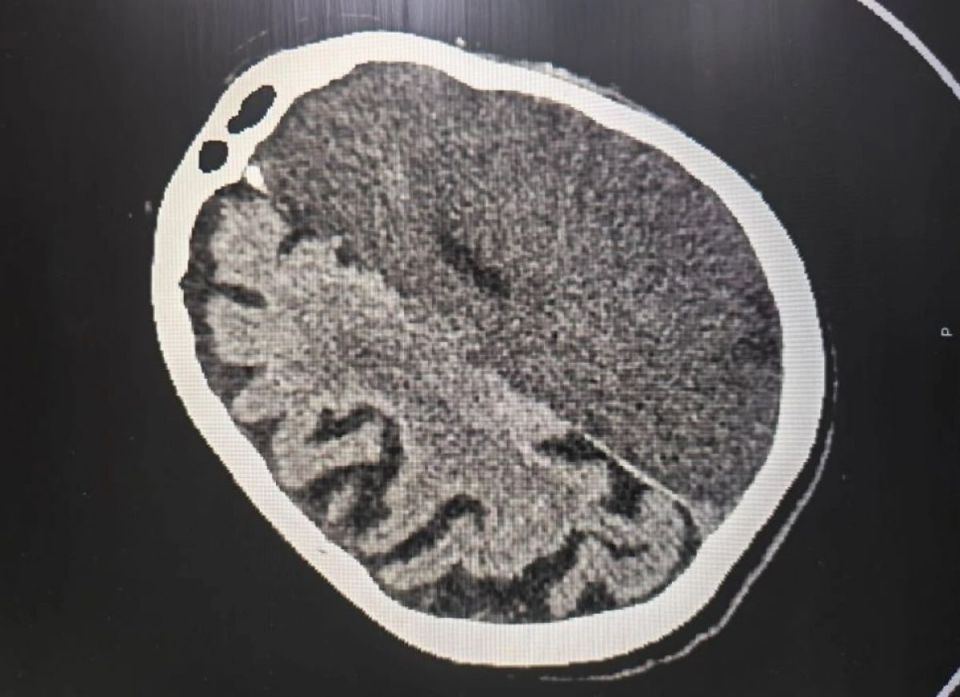

76-летняя пациентка поступила в реанимацию в критическом состоянии. Накануне вечером у неё внезапно ослабли руки и ноги, но вызывать «скорую» женщина решилась только на следующее утро. К моменту госпитализации правая сторона её тела уже была...